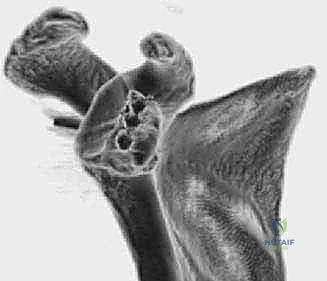

الشكل 1 • يعتمد ثبات الكتف على تفاعل المثبتات الديناميكية والساكنة للأنسجة الرخوة. كما يلعب التركيب العظمي للتجويف الحقاني وعظم العضد دورًا حاسمًا في الحفاظ على استقرار المفصل.

الشكل 3 • تقييم دقيق لحجم العظم المفقود من الحافة الأمامية للتجويف الحقاني، وهو المعيار الأساسي لتحديد نوع التدخل الجراحي المطلوب.

الشكل 5 • صورة مقطعية ثلاثية الأبعاد (3D CT) تظهر بوضوح التآكل الشديد والفقدان العظمي في الحافة الأمامية السفلية للتجويف الحقاني، مما يؤكد الحاجة الماسة للترقيع العظمي.